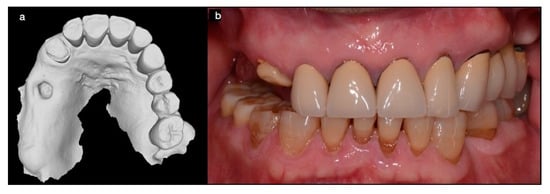

3.1. SCAI Approach Clinical Case